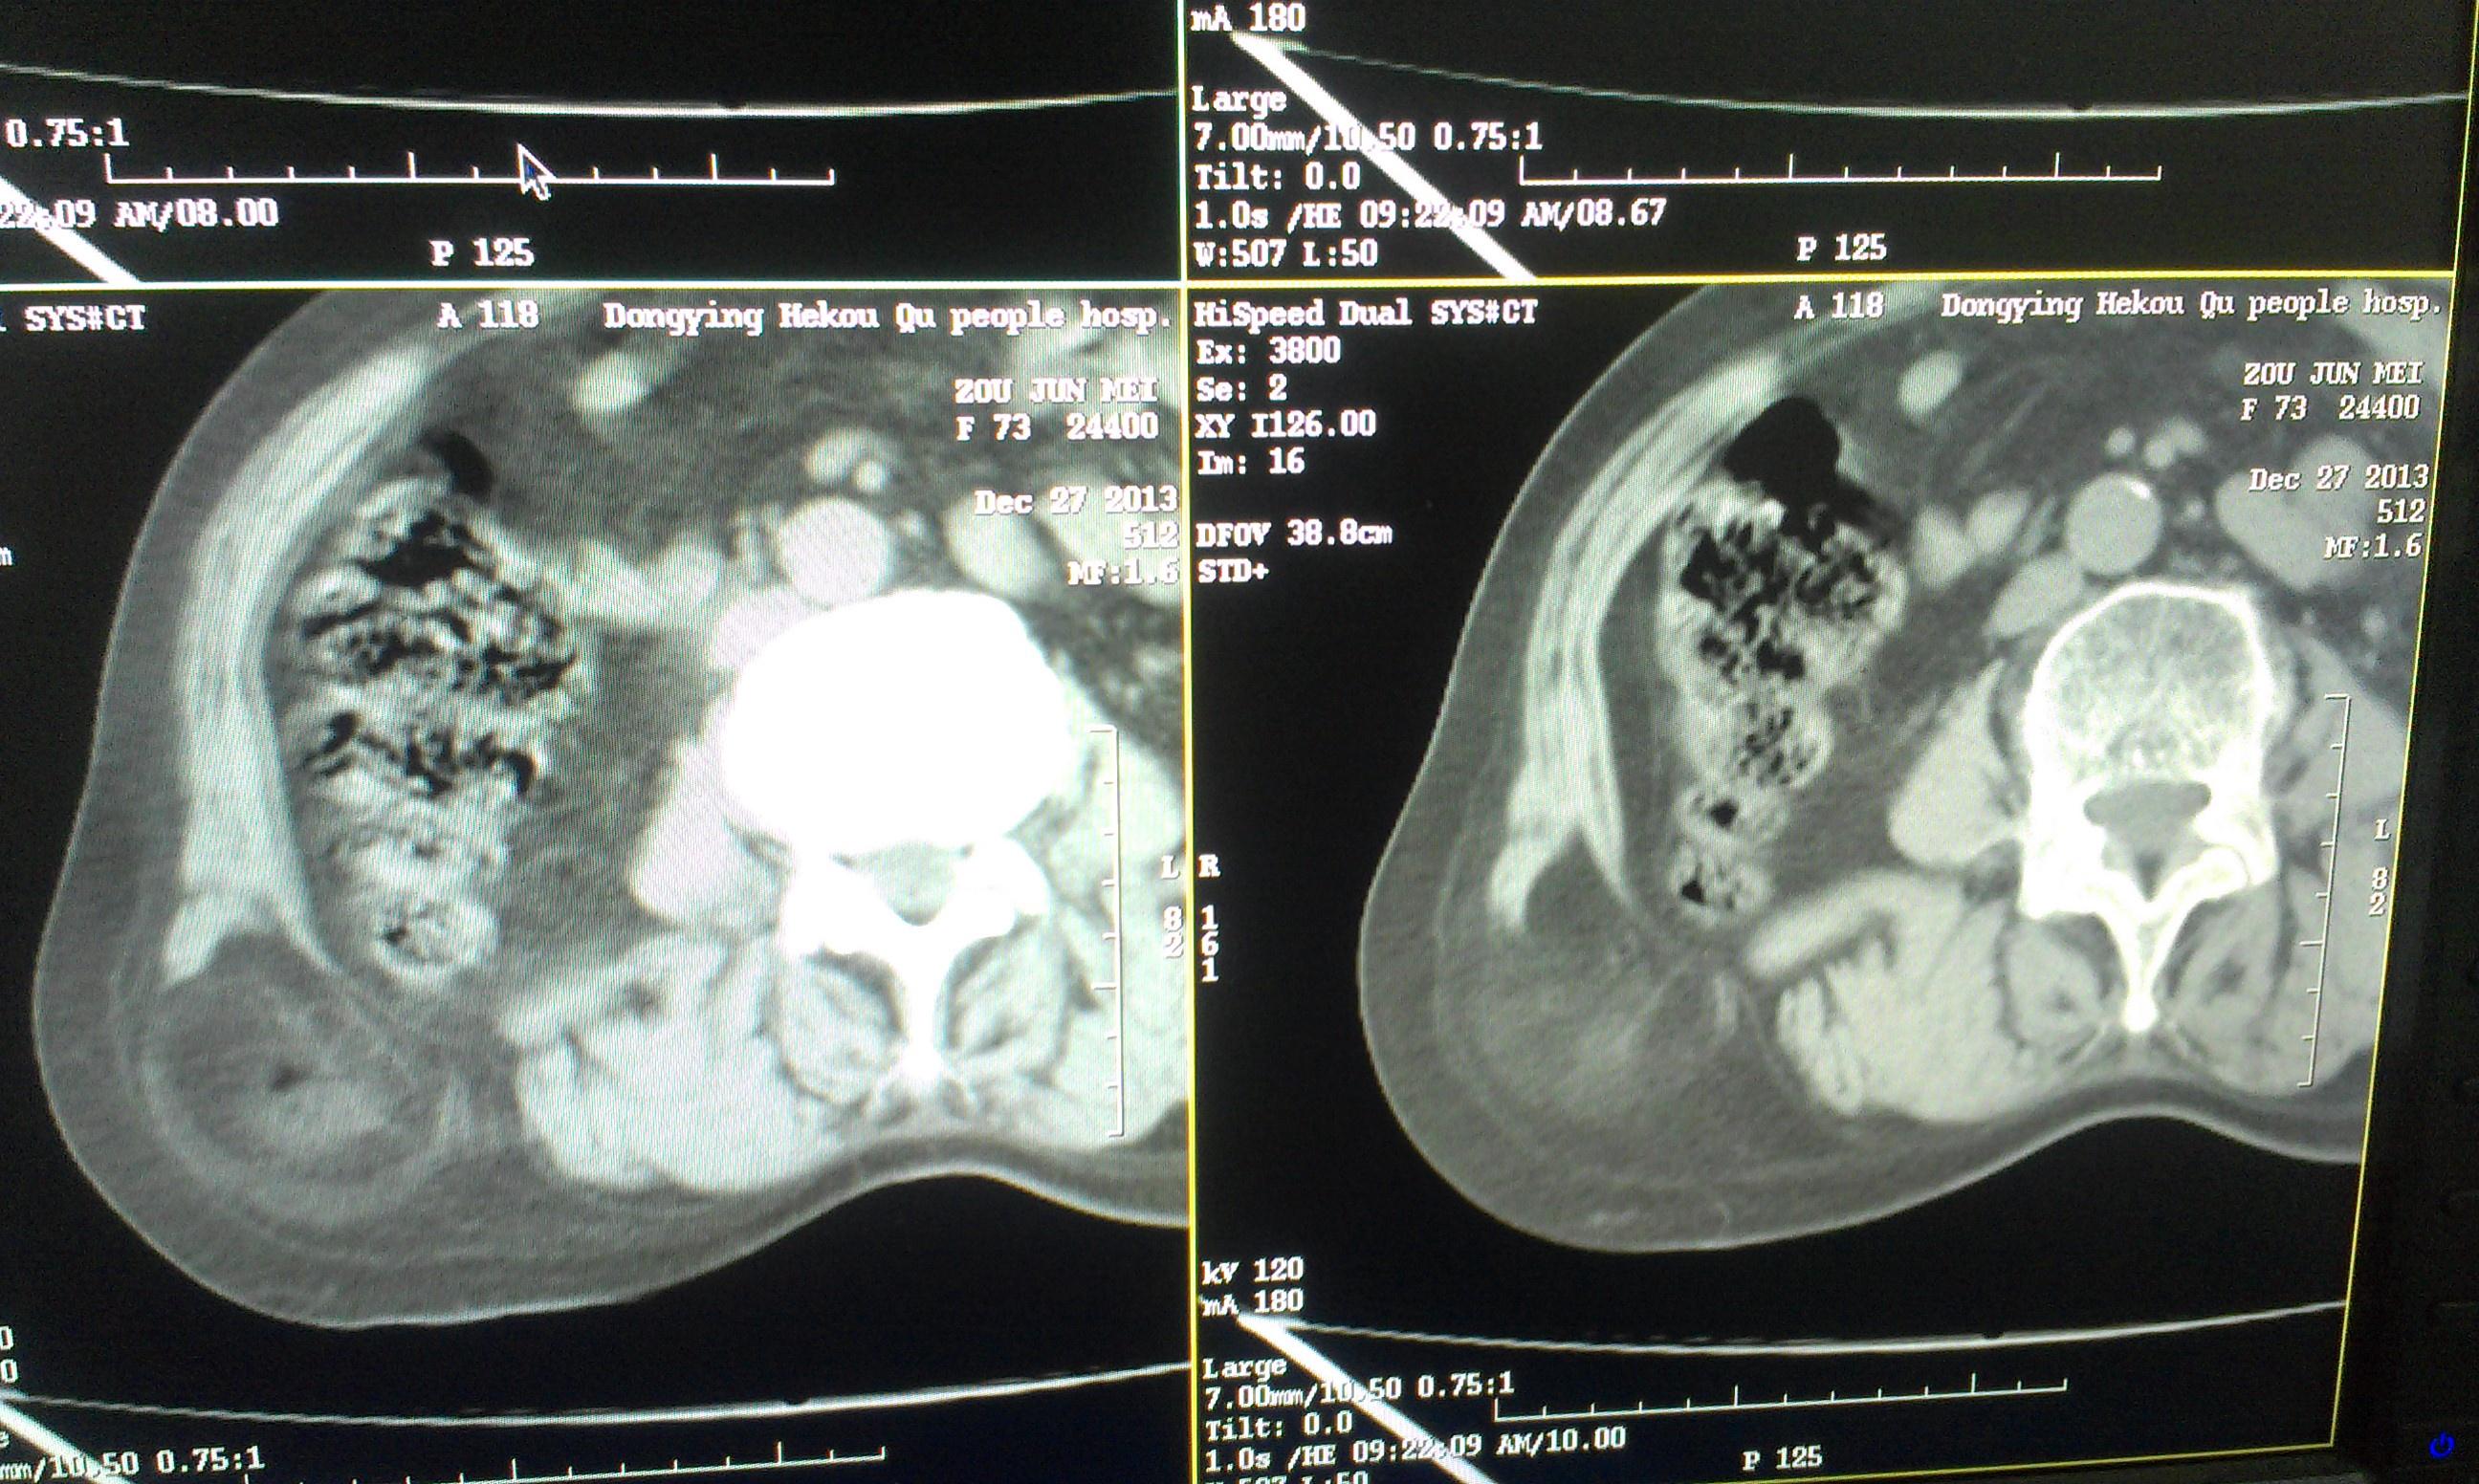

挺经典的腰疝

右腰部包块,随呼吸可运动。

非常经典的ct片,不知是继发于何种原因还是先天性的?里面内容物一般是肠管,很少发生较窄、嵌顿。